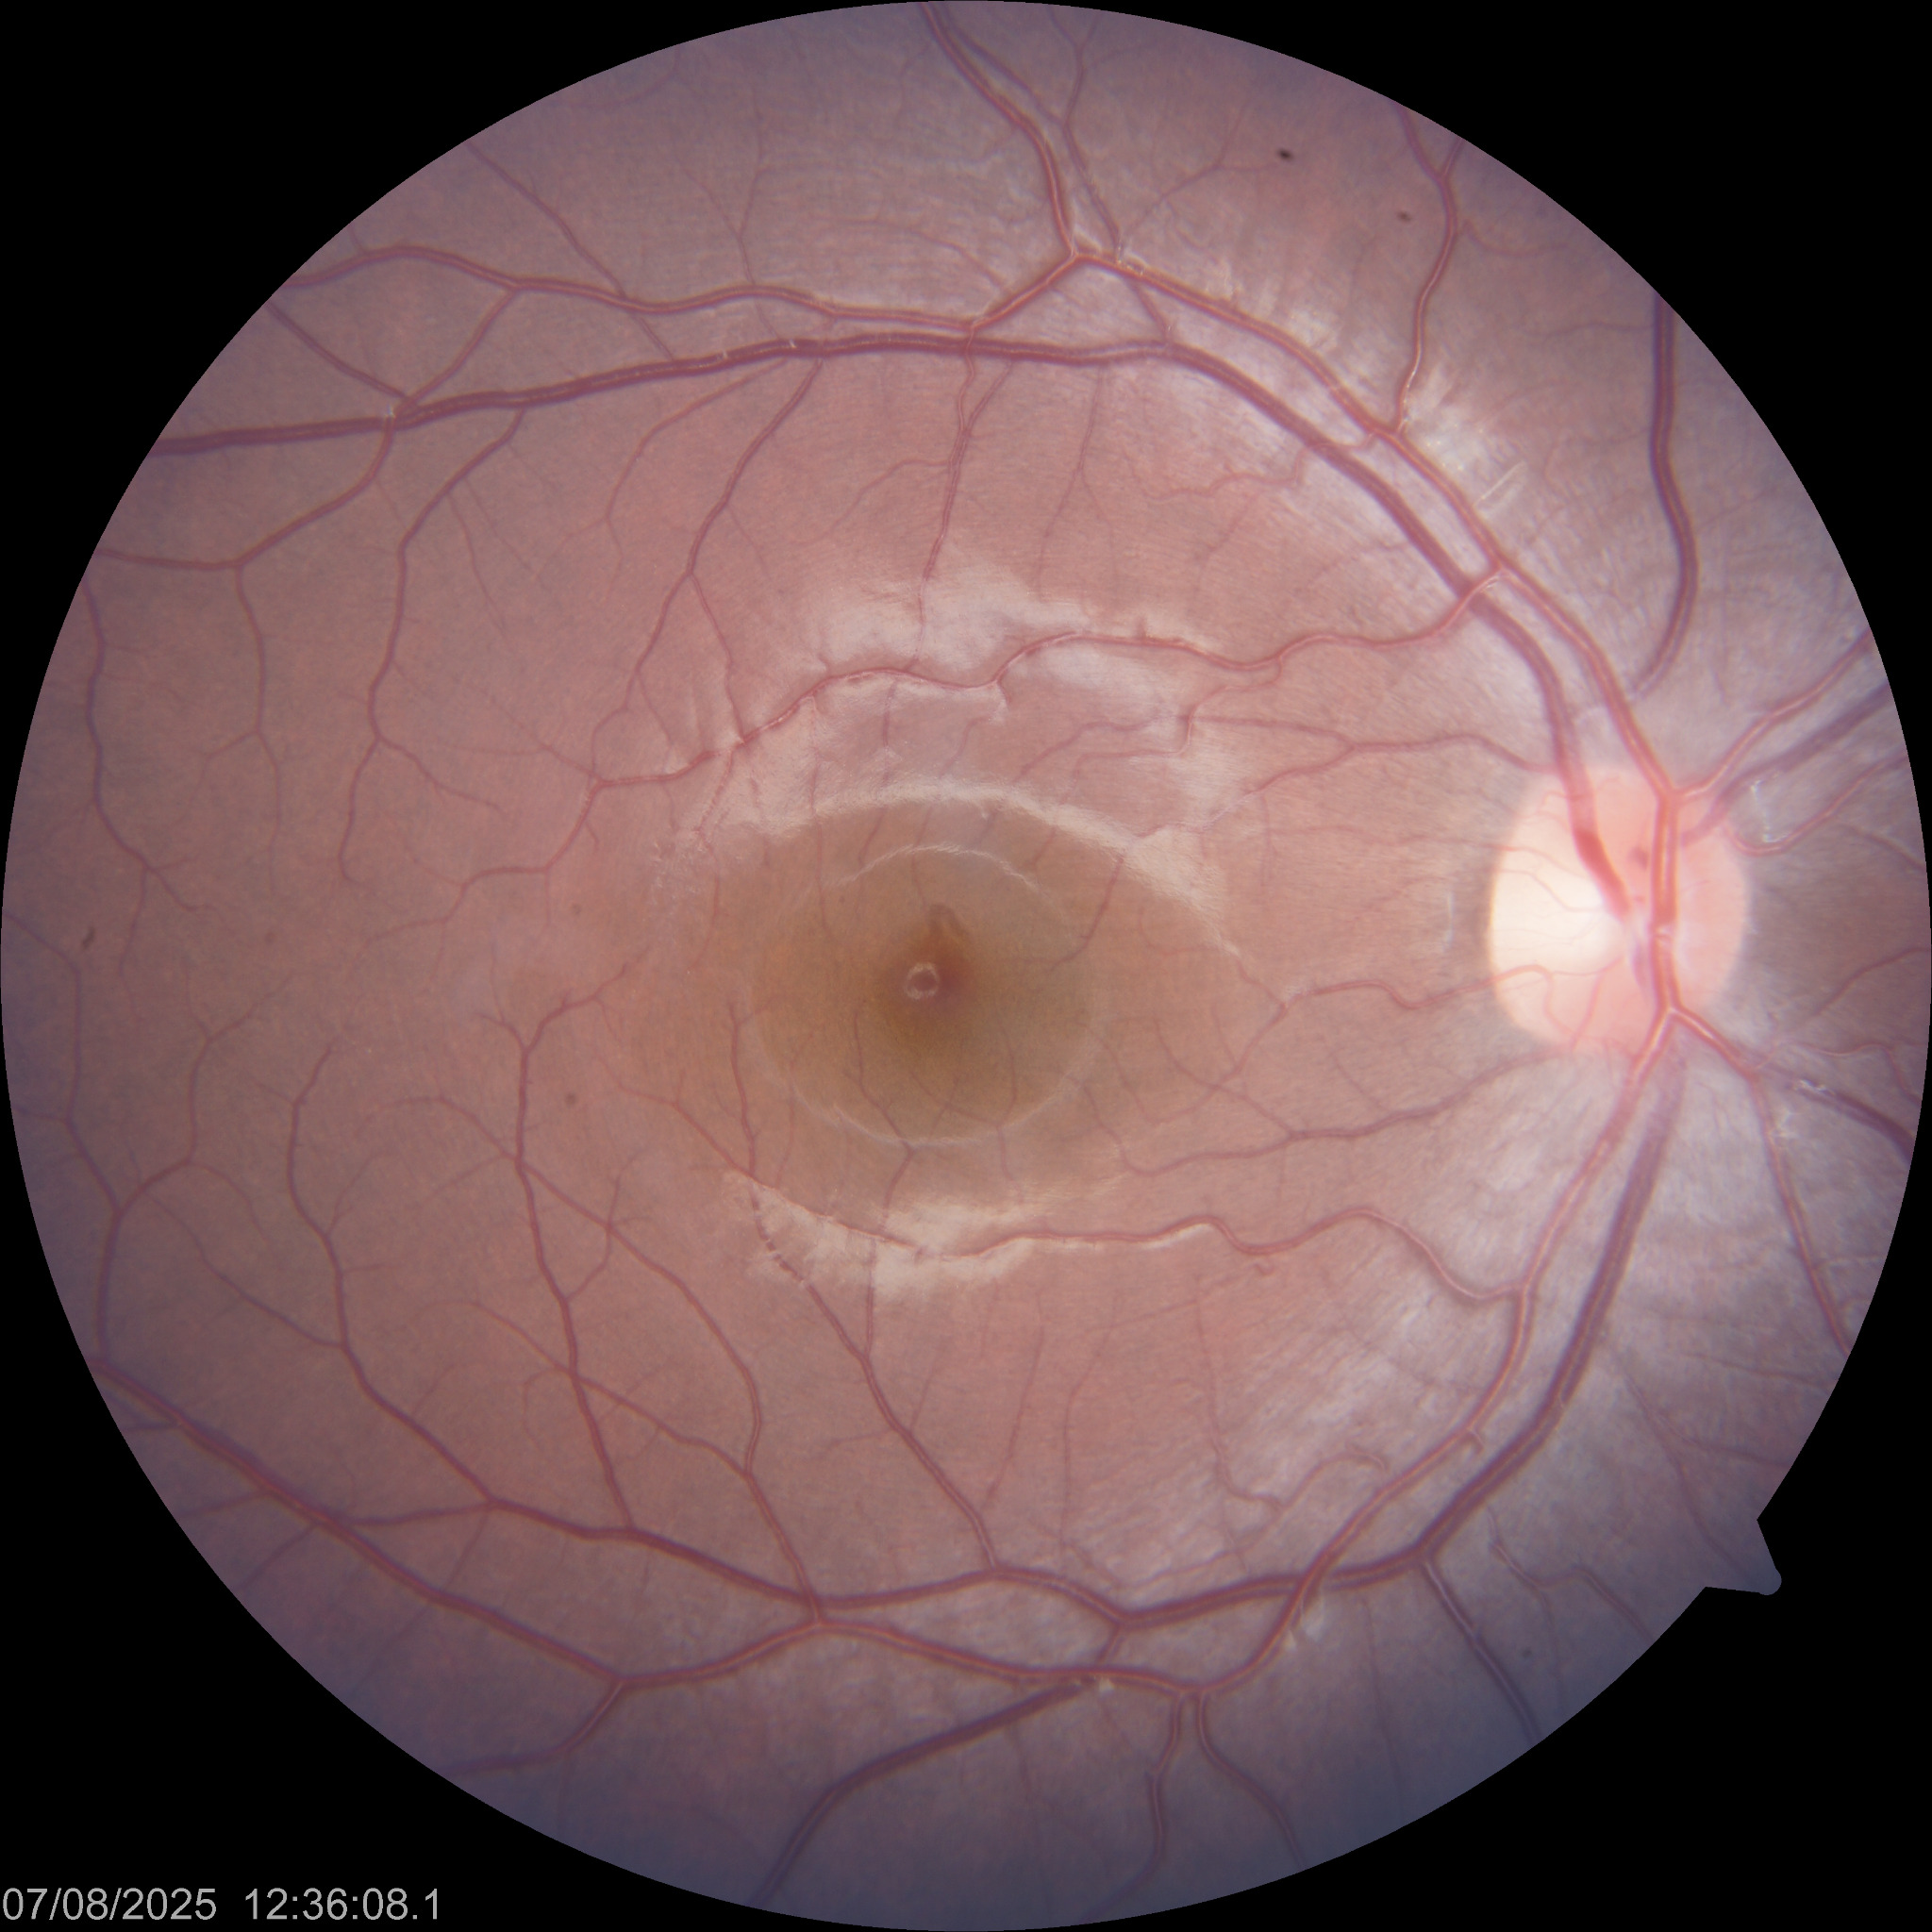

E d e m a m a c u l a r

COLOR